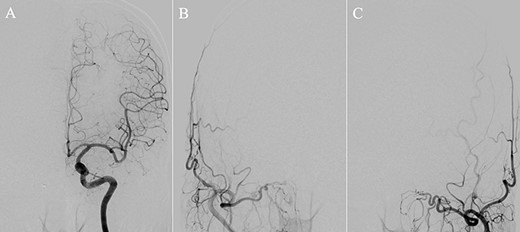

A patient in their 70s with extracranial lymphoma was incidentally found to have ACF–dAVF via head computed tomography and magnetic resonance angiography. Digital subtraction angiography (DSA) confirmed ACF–dAVF with multiple feeding branches, arising from bilateral OphAs, distal IMAs and the left middle meningeal artery (MMA), with cortical venous reflex (Borden type III, Cognard type IV) (Fig. 1). At the patient’s request, we chose endovascular, rather than surgical, treatment. We injected a 20% N-butyl-2-cyanoacrylate (NBCA)–lipiodol mixture into the fistula through bilateral ethmoidal arteries and the left MMA after we placed coils at the terminal branch of the right OphA. However, we could not achieve full penetration into the fistulous connections because of pressure secondary to high flow from the IMA branches, which resulted in incomplete obliteration (Fig. 1). Four months later, we repeated TAE by temporarily reducing nasal blood flow by inserting gauze infiltrated with xylocaine and epinephrine into the nasal cavities. After introducing the guiding catheter, an endonasal surgeon inserted X-ray-detectable surgical gauze infiltrated with 1% xylocaine and epinephrine (1:10 000) into bilateral nasal cavities using a nasal speculum, while paying full attention to avoid damage to the nasal mucosa. Then, we confirmed that the gauzes were placed in appropriate locations in the upper nasal cavity under fluoroscopic guidance. Immediately after insertion, we were able to confirm decreased blood flow from the IMA using DSA (Fig. 2). After this procedure, we navigated a DeFrictor Nano Catheter (Medico’s Hirata, Osaka, Japan) into the terminal branch of the OphA, which was connected to the dorsal nasal artery. Even though there was still a distance from the tip of the microcatheter to the shunt pouch, the NBCA reached the shunt point and penetrated the venous portion (Fig. 3). Follow-up DSA demonstrated complete obliteration of the ACF–dAVF, and blood flow in the nasal mucosa from the IMA branches recovered normally (Fig. 4).

(A) Inserting gauze infiltrated with epinephrine into bilateral nasal cavities. (B and C) Radiograph showing the gauze inserted toward the upper nasal cavity. (D) DSA before inserting the gauze, anteroposterior view, showing blood flow from the right distal IMA. (E) DSA immediately after inserting the surgical gauze, anteroposterior view, showing decreased blood flow from the IMA. (F) Schematic drawing of remaining (red solid line) and occluded feeding arteries (black dotted line) after inserting the surgical gauze. Schema describing that the left dorsal nasal artery (asterisk) remained patent after embolizing the left middle meningeal artery (1), bilateral ethmoid arteries (2) and the right dorsal nasal artery (3), and blood flow from bilateral distal IMAs (4) decreased using our transnasal flow reduction method. (5) Angular artery.